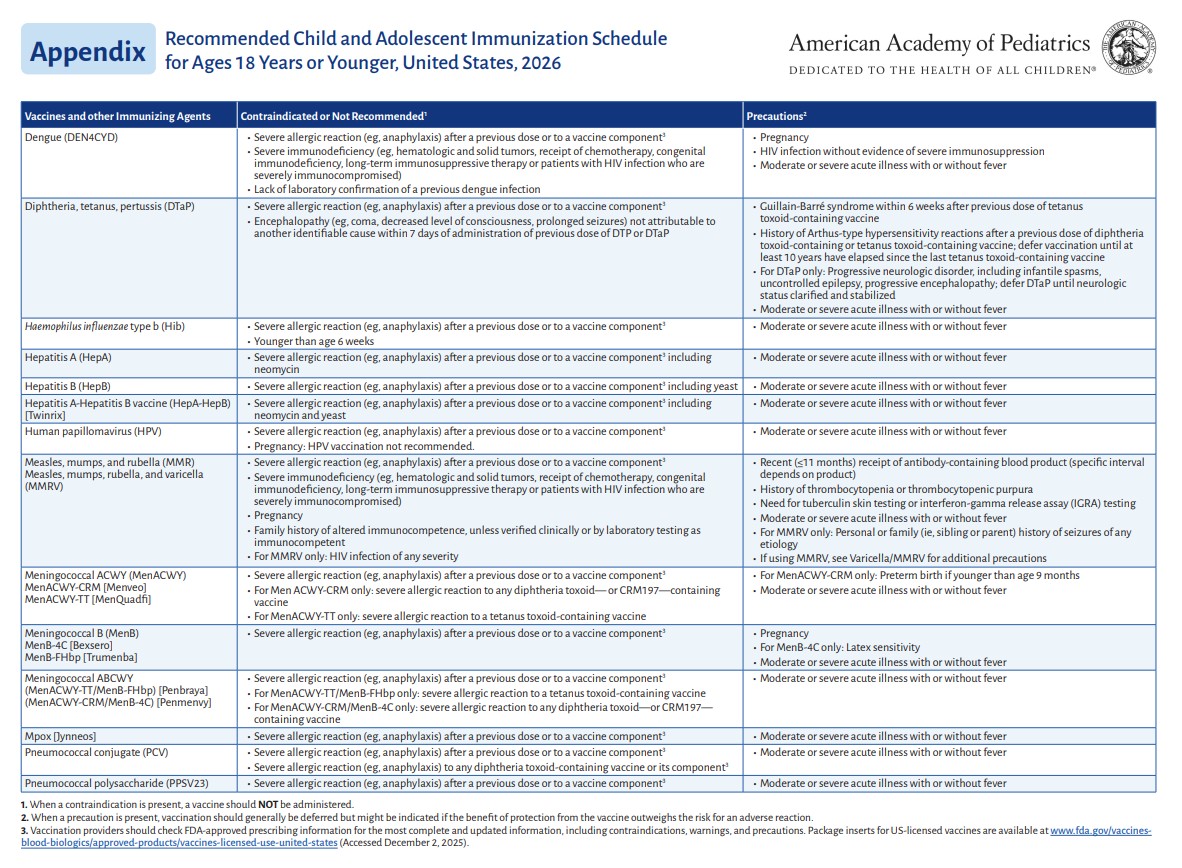

p 7

p 8